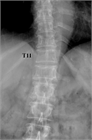

1. がんの既往のある患者が脊椎に痛みを訴えた場合、転移性脊椎腫瘍を念頭に置くことが推奨される(推奨度1)

1. 転移性脊椎腫瘍を疑った場合、全身の造影CTを撮影することが推奨される(推奨度1)

1. 転移性脊椎腫瘍と診断した場合、余命を評価することが推奨される(推奨度1)